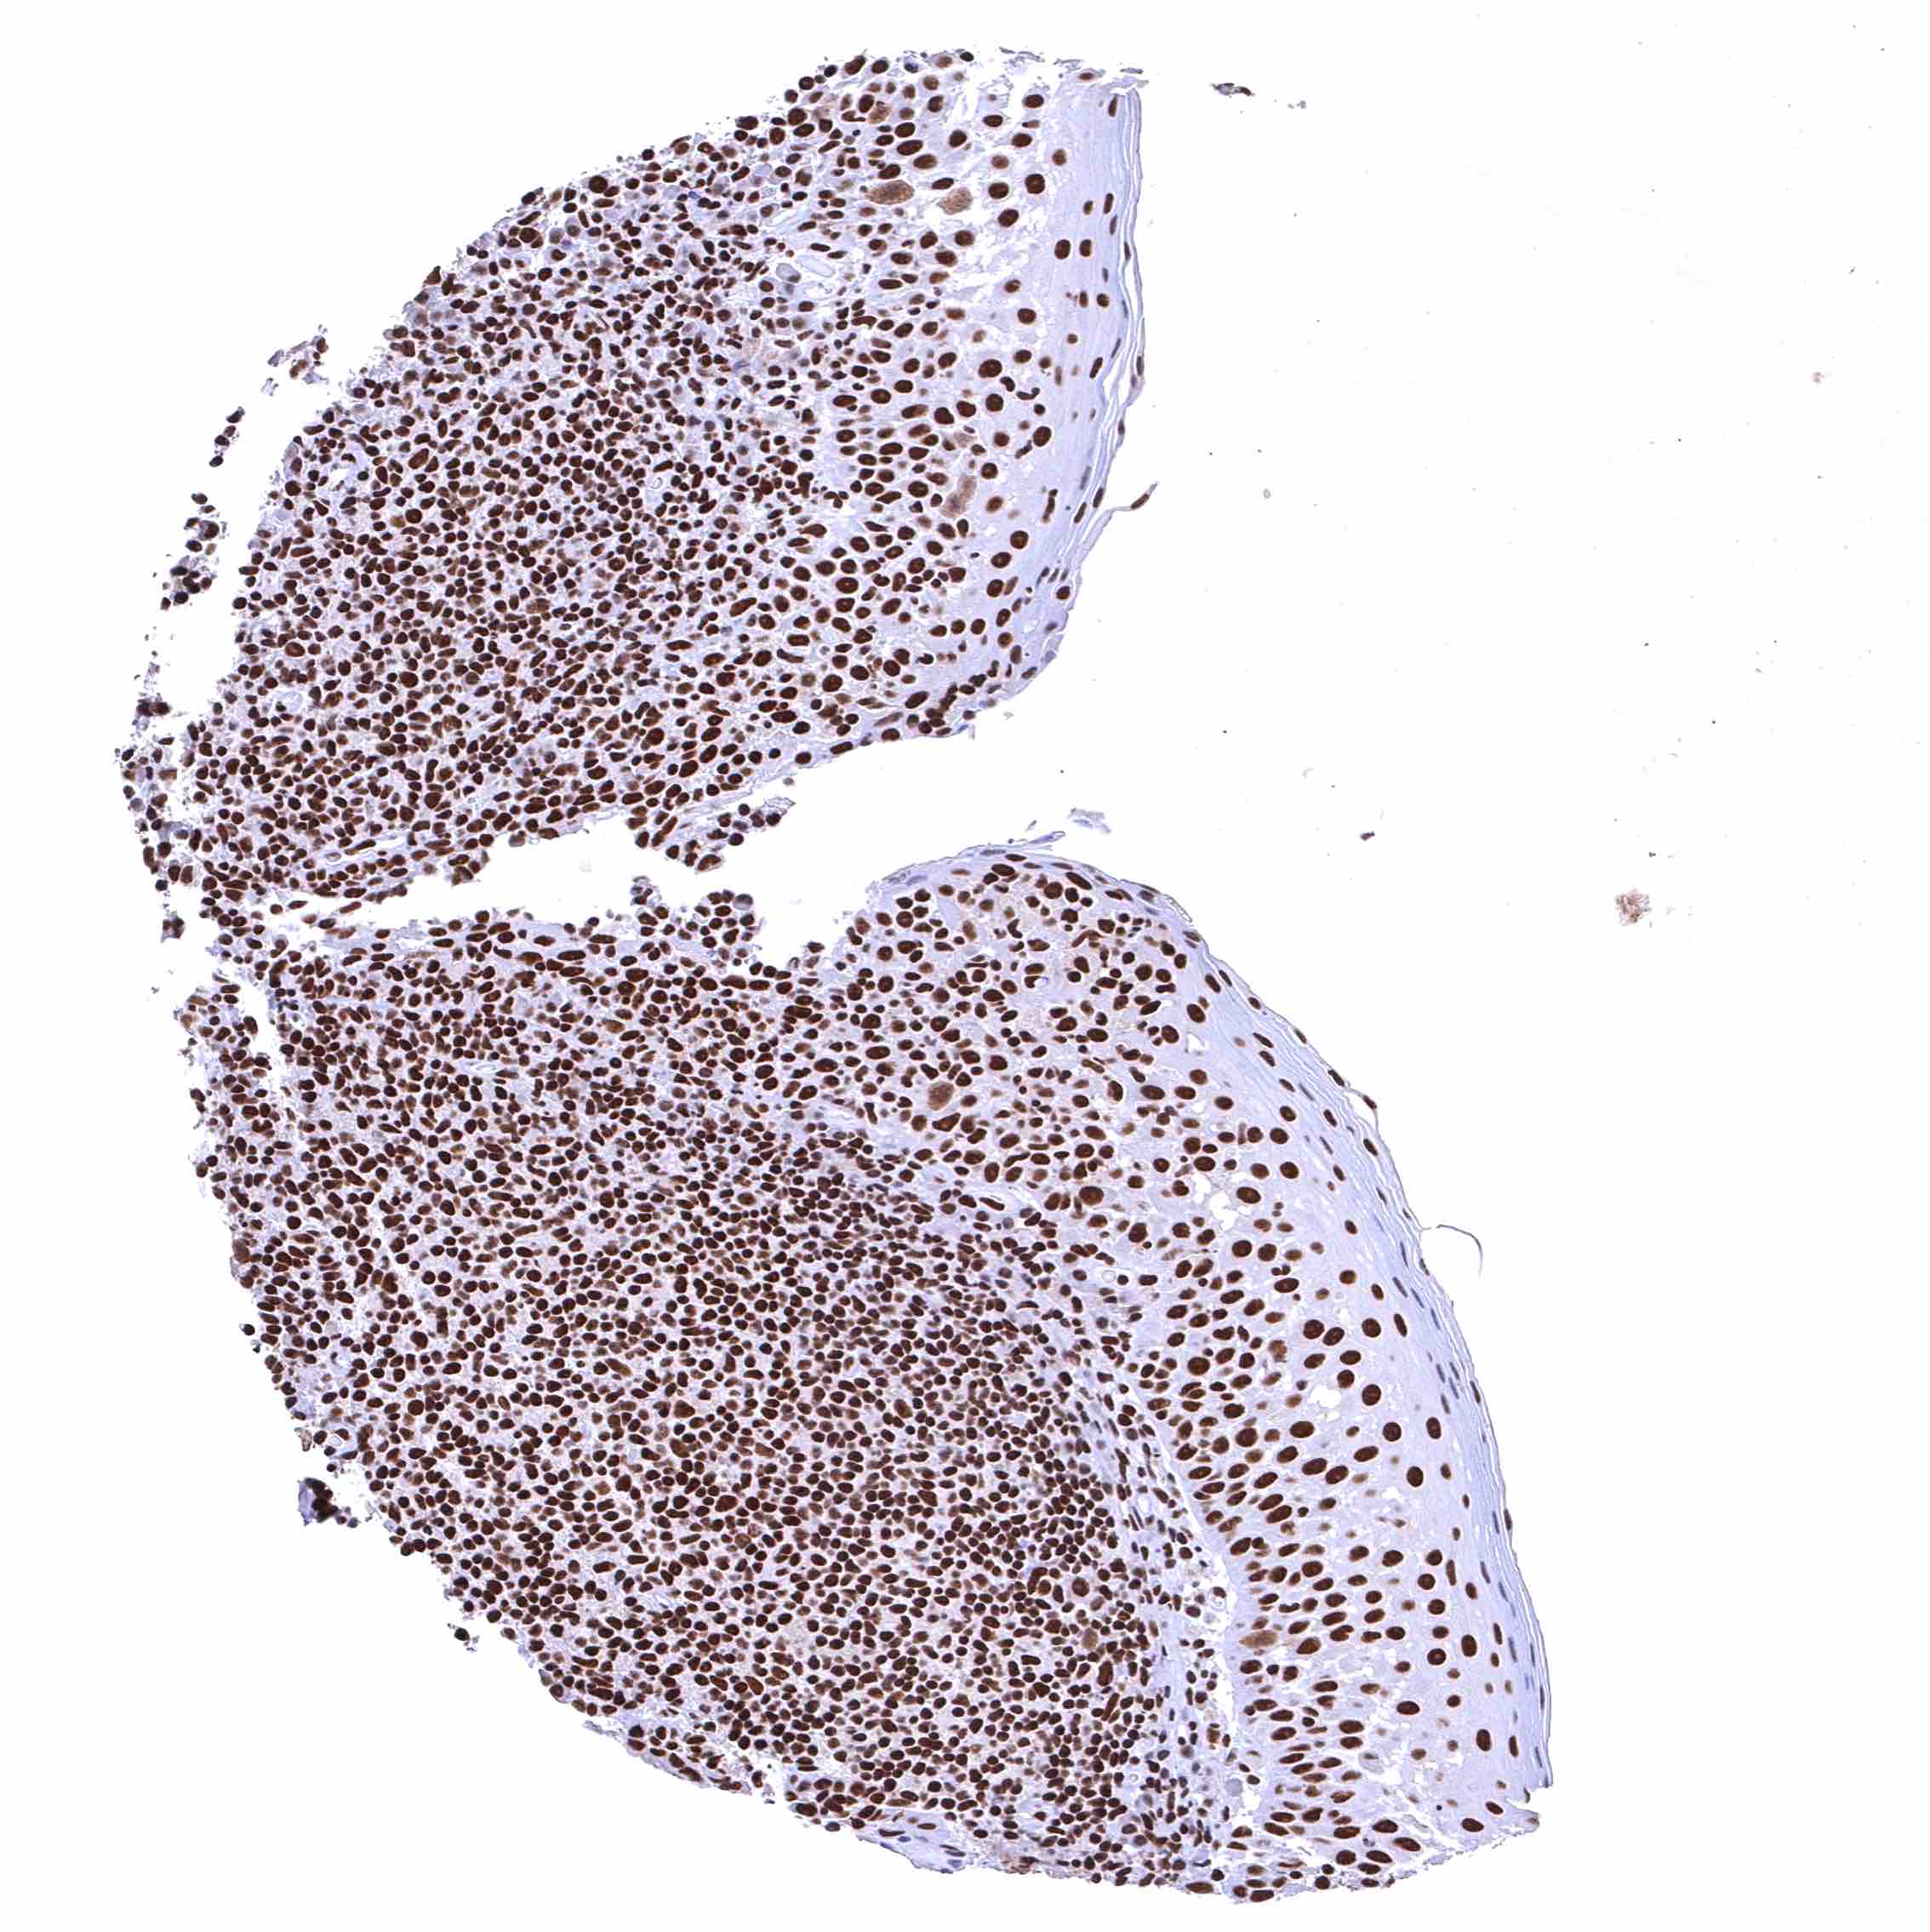

BRD4 antibody [HMV4275] HistoMAX™

Tonsil – Strong nuclear BRD4 staining of all cell types.